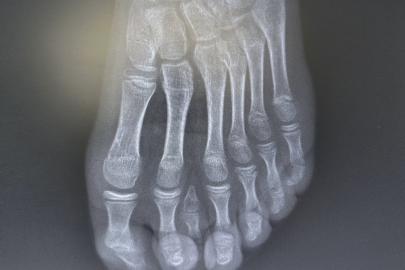

Batman'da nadir 7 parmaklı ayak vakası başarıyla tedavi edildi